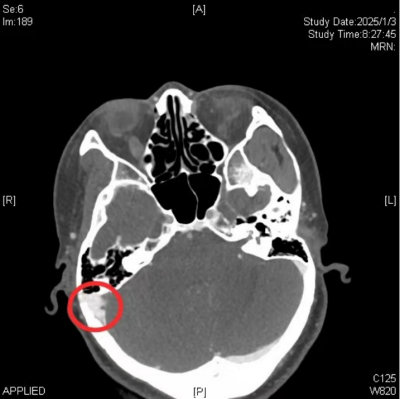

龚巍解释,搏动性耳鸣是一种由头颈部器官、心血管或其他结构异常所产生的声音,通过骨结构、血管或血流传送至内耳,使患者感受到与心跳一致的节律性声音。这种耳鸣分为血管源性和非血管源性两种。血管源性搏动性耳鸣主要由血管结构异常或血流加速导致血流紊乱所产生;而非血管源性搏动性耳鸣则可能由腭帆、鼓膜张肌、镫骨肌等肌肉的阵挛、咽鼓管异常开放、颞颌关节病等因素引起。张莲花的高分辨率CT扫描提示了其可能病因:她右耳的乙状窦存在憩室,突入右侧乳突气房,而这可能是她搏动性耳鸣的“罪魁祸首”。

术前CT提示(图注部位):右侧乙状窦突入乳突气房形成憩室